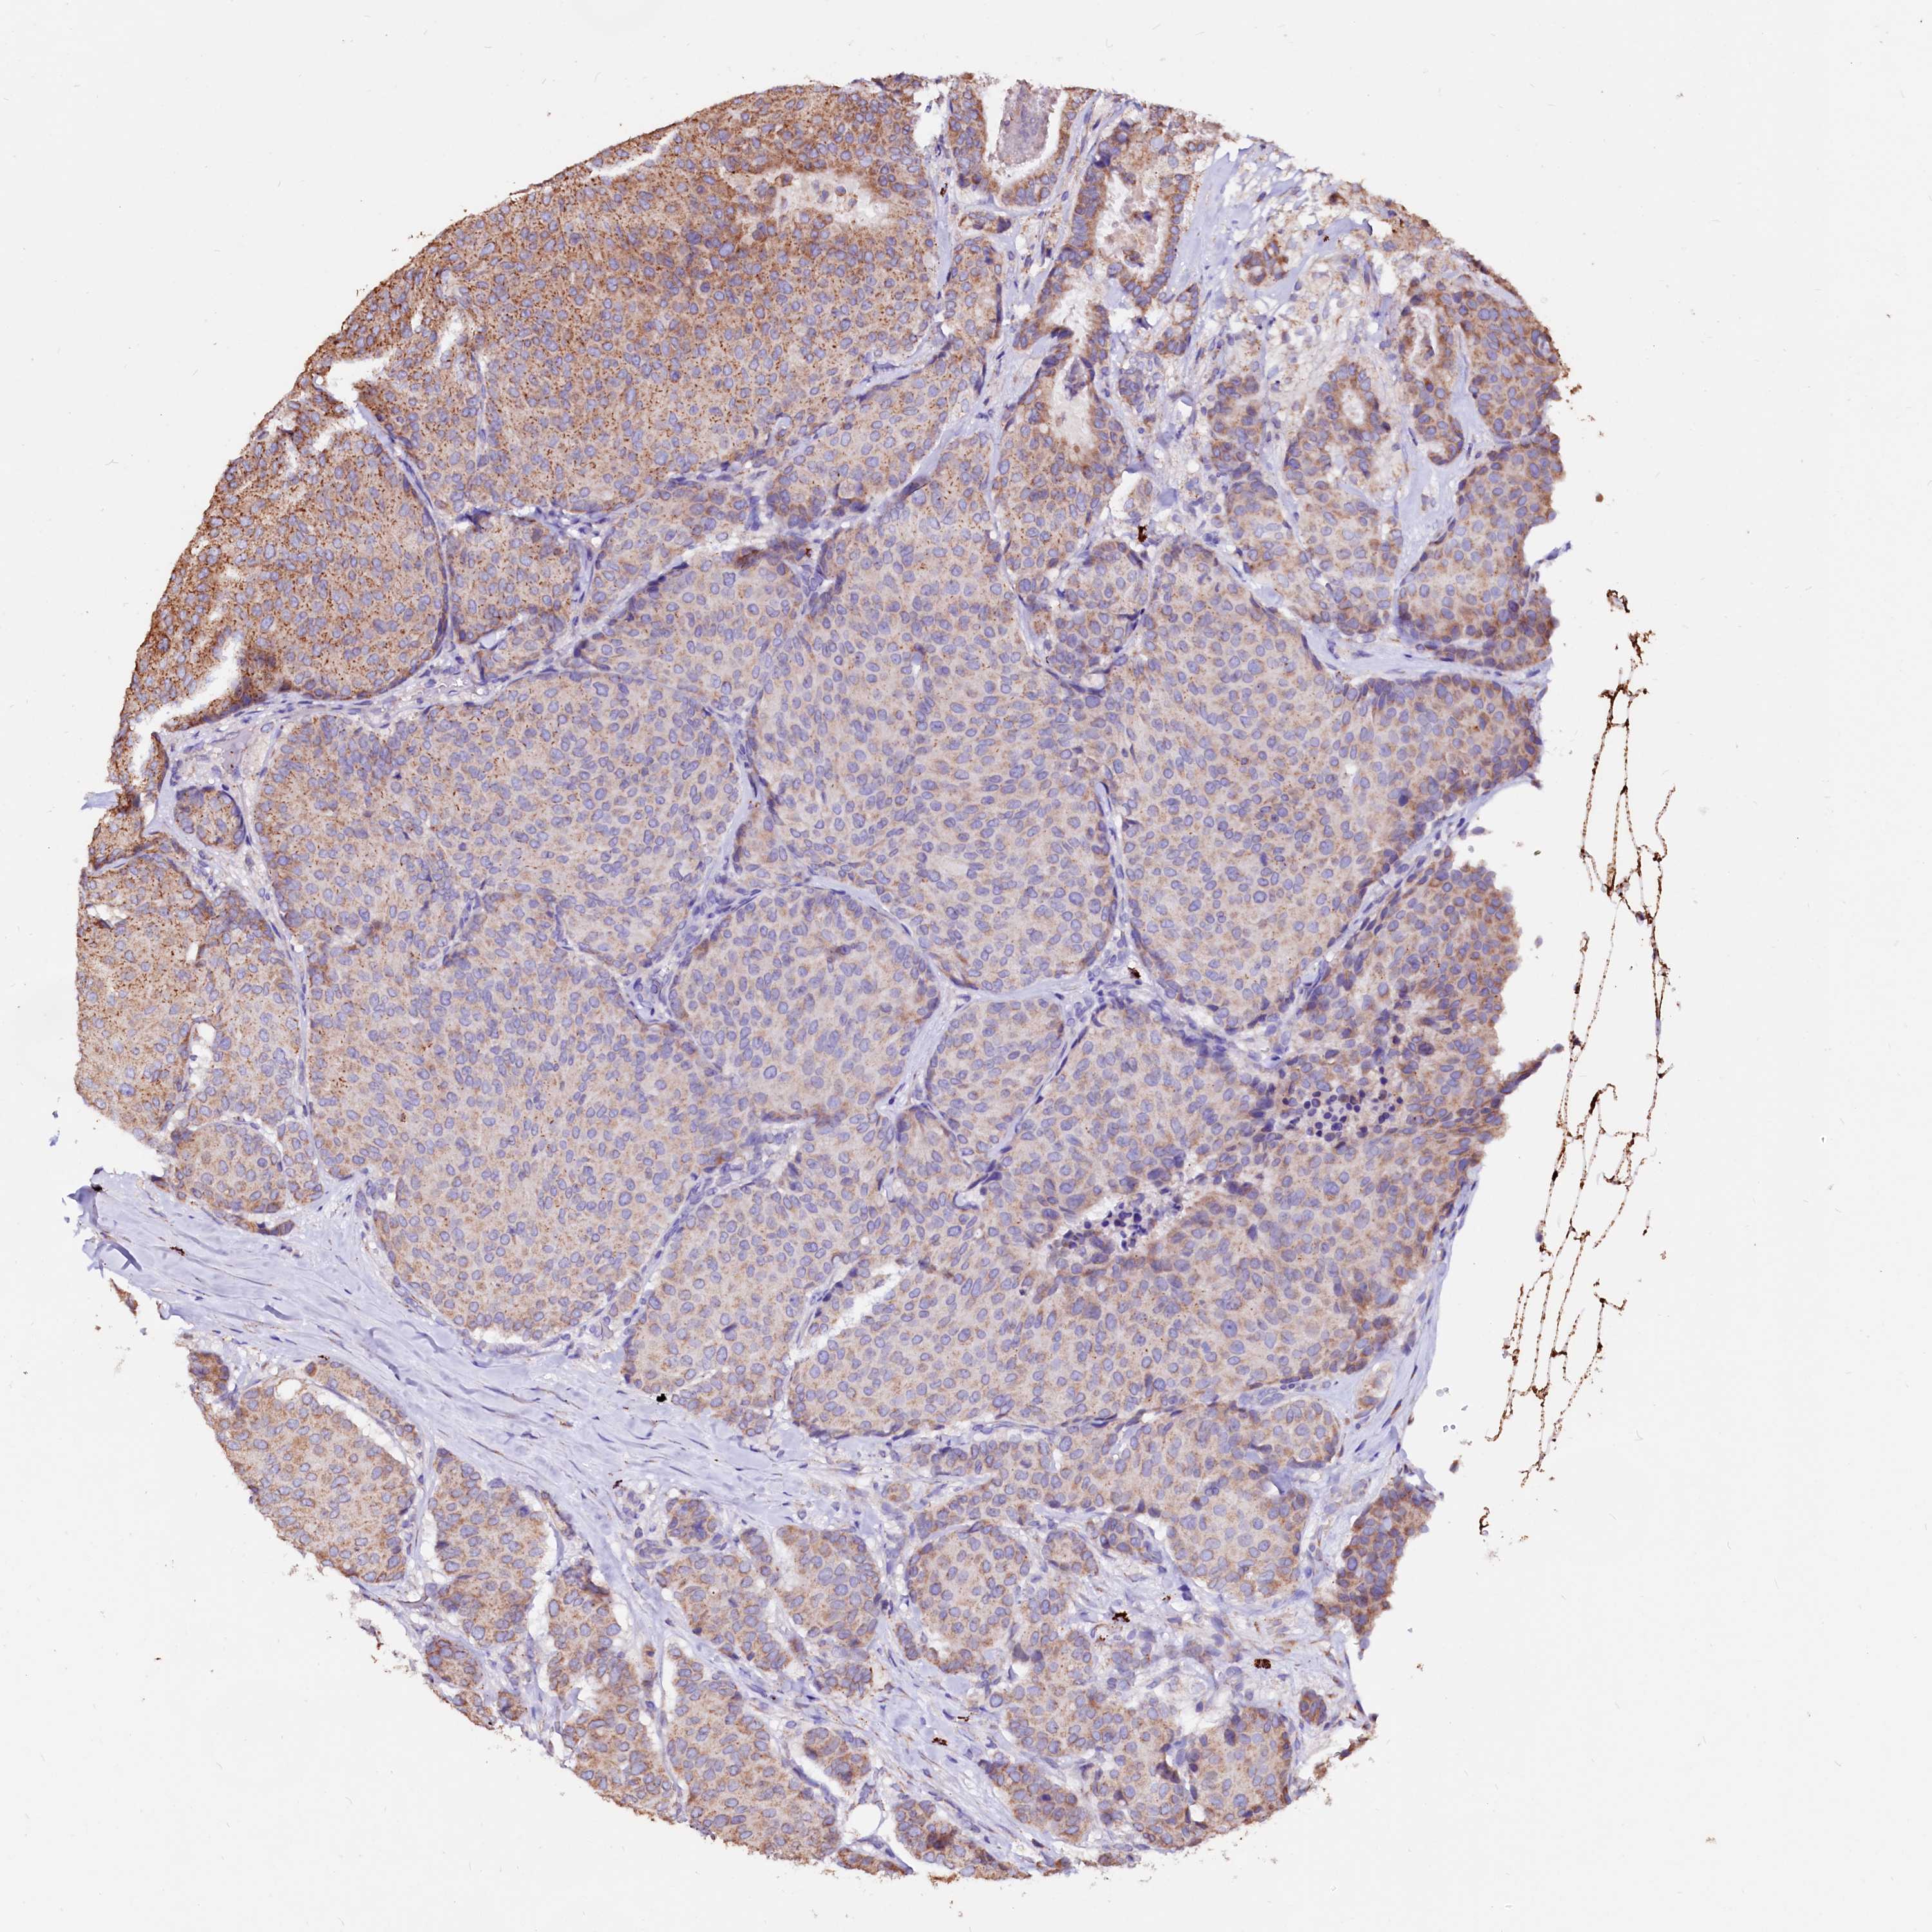

CANCER BREAST CANCER Show tissue menu

BRCA TCGA BRCA VALIDATION PROTEIN EXPRESSION